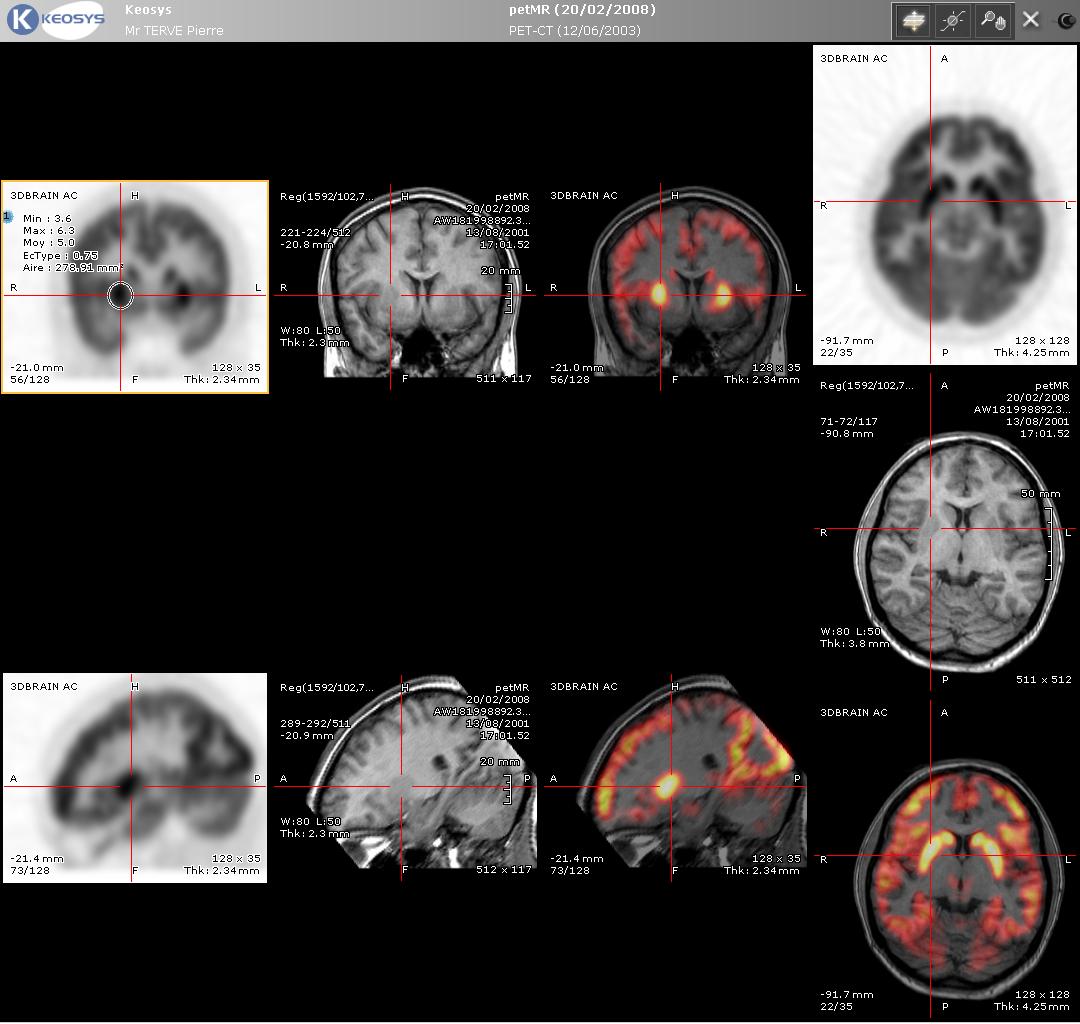

5. PET-CT 및 PET-MRI

PET-CT는 PET와 CT를 결합한 장비로, 해부학적 정보와 대사 정보를 함께 얻을 수 있어 유용하다. 최신 PET 스캐너는 고급 멀티 검출기 배열 CT 스캐너와 통합되어 제공되며(PET-CT), 동일한 세션에서 두 스캔을 순차적으로 수행할 수 있다. 환자는 위치를 변경하지 않아도 되므로 두 영상이 정확하게 등록되어, PET 영상의 이상 부위가 CT 영상의 해부학적 구조와 더욱 완벽하게 연관된다. 이는 움직이는 장기나 구조의 상세한 뷰를 보여주는 데 매우 유용하다.

율리히 연구소에서는 2009년 4월 세계 최대 규모의 PET-MRI 장치가 가동을 시작했다. 이 장치는 9.4-테슬라 MRI 장치와 PET가 결합된 것이다. 현재 이러한 높은 자기장 세기에서는 머리와 뇌만 영상화할 수 있다.[72] 뇌 영상의 경우, N-로컬라이저라는 장치를 사용하여 통합 PET-CT 또는 PET-MRI 스캐너 없이 CT, MRI 및 PET 스캔을 등록할 수 있다.[73][74][75][76]